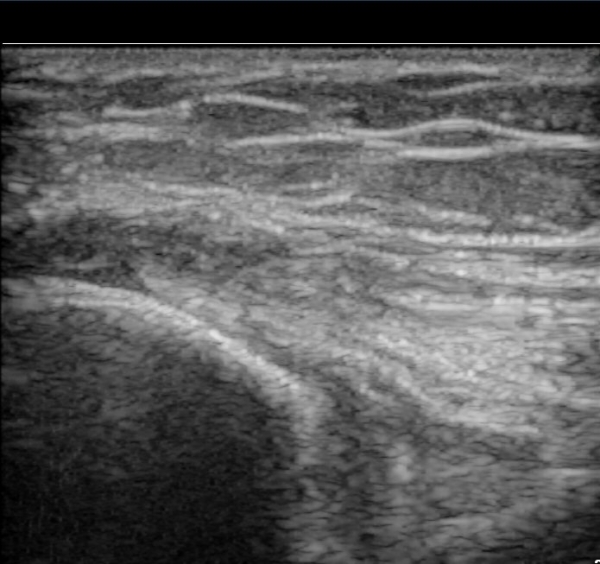

ÃÊÀ½ÆÄ °Ë»ç

³»»ó°ú Á¾´Ü¸é°Ë»ç¿¡¼­ ³»»ó°ú ±¼°ñ°Ç ºÎÂøºÎ¿¡ Àú¿¡ÄÚ º´º¯ÀÌ °üÂûµÈ´Ù. °Ç ½ÉºÎÀÇ

³»ÃøºÎÀδë´Â ƯÀÌ ¼Ò°ßÀ» º¸ÀÌÁö ¾Ê´Â´Ù(±×¸² 1, 2).